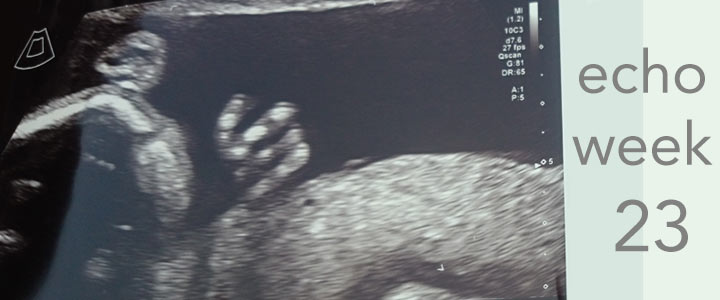

De gedetailleerde echo in het ziekenhuis in Rheine werd gedaan door een professor en was echt bijzonder en lekker lang. Ze hebben alles uitgebreid gemeten en alle organen bekeken. We konden heel uitvergroot haar hartje zien en horen. De kamers en boezems alles was duidelijk te zien. Kreeg na afloop alle papieren mee van de metingen, allerlei grafieken, waar je uit kon lezen dat alles tip top in orde is.